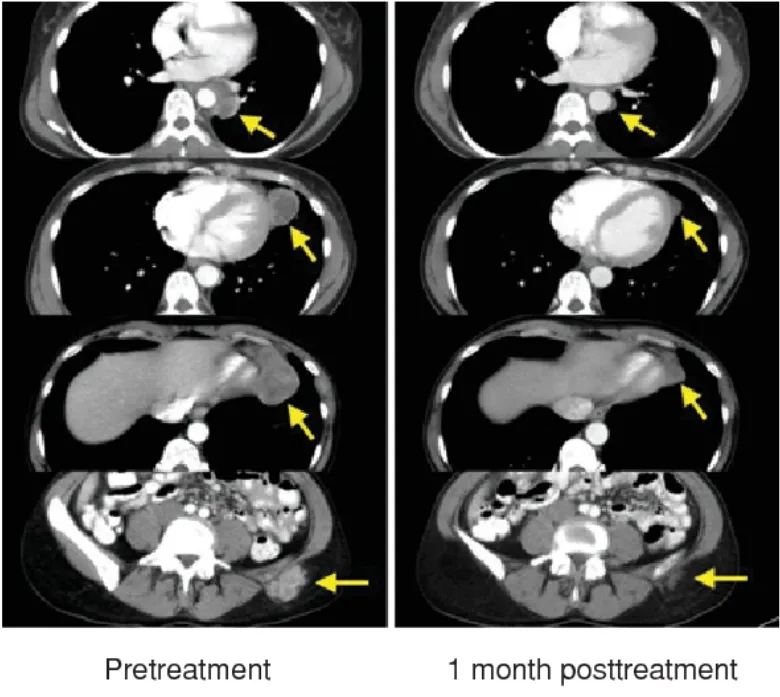

治疗1个月完全缓解(三)

第三位晚期黑色素瘤患者出现纵隔、肺、淋巴结和皮下转移,接受TIL治疗后仅1个月快速消退,最终完全缓解!